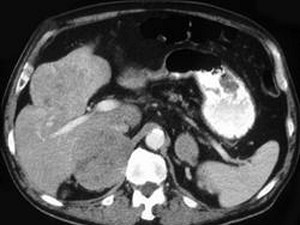

男性,60岁,曾患乙肝,肝硬化多年,右上腹胀痛1月余,AFP为80.8μg/L,CT检查如图所示,最佳的诊断是 ( ) CY-00021.jpg CY-00022.jpg

• A.肝腺瘤、右肾上腺腺瘤

• B.肝结节性增生、右肾上腺瘤

• C.肝、右肾上腺均为转移瘤

• D.肾上腺癌肝转移

• E.肝癌右肾上腺转移